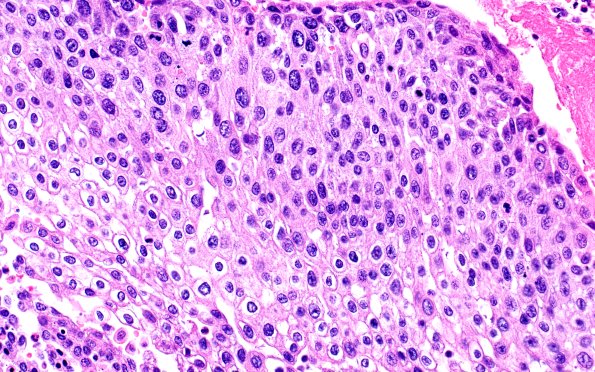

23B3 Heart (Case 23) H&E 1GRV3 40X

The tumor has a squamous appearance and numerous mitotic figures. (H&E)